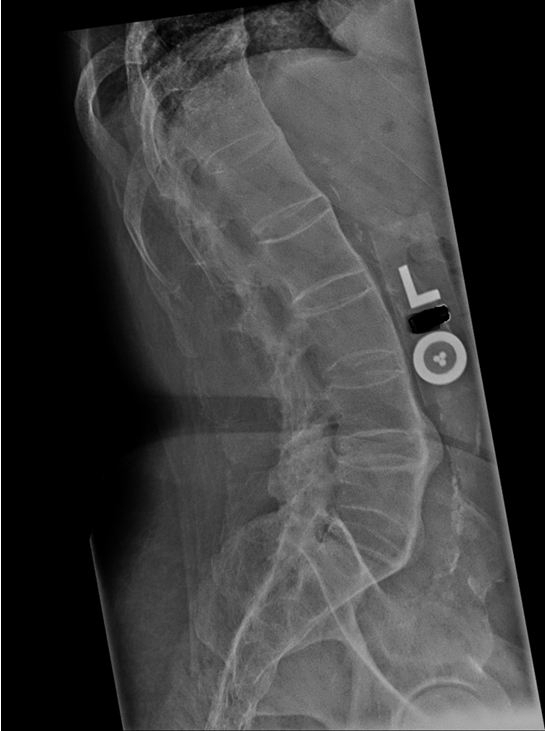

Lower back pain

Bony metastases typically cause pain that is constant and worse at night, with point tenderness on examination. In contrast, the pain caused by degenerative disease is typically exacerbated by exercise and relieved by rest.

Vertebral osteomyelitis may cause chronic progressive pain with point tenderness over the affected vertebrae. However, it is typically accompanied by a low-grade fever and generally occurs in patients with recent overlying soft tissue infection or bacteremia. The erythrocyte sedimentation rate (ESR) and C-reactive protein (CRP) levels are usually elevated.

Lumbar strain usually occurs acutely following twisting of the back while lifting heavy weights. It is typically exacerbated by activity and relieved by rest, and there is usually no point tenderness.

Iliac artery thrombosis can cause low back pain associated with claudication of the hip muscles and possibly impotence.